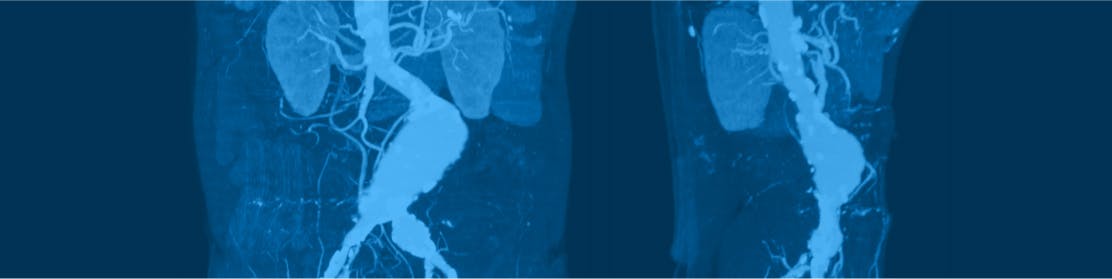

Embolizarea splenică este o procedură minim-invazivă efectuată prin tehnici de Radiologie Intervențională care tratează hemangiomul splenic sau hipersplenismul.

Embolizarea splenică este o intervenție minim invazivă, endovasculară cu ajutorul căreia sunt tratate hemangioamele splenice sau hipersplenismul (splină mărită).

La nivelul mâinii (artera brahială) sau după caz, a piciorului (artera femurală), medicul radiolog intervenționist va face o anestezie locală cu xilină. Apoi va puncționa artera aleasă ca abord pentru a introduce catetere (fire lungi foarte subțiri) pe care le va folosi pentru a naviga prin arteră până la nivelul arterele splenice. Aici, medicul va injecta substanță de contrast pentru a putea vizualiza întregul sistem vascular și în particular, arterele care irigă hemangiomul/splina.

La acest nivel, medicul radiolog intervenționist identifică vasele de sânge care alimentează hemangiomul sau în funcție de caz, arterele splenice cu potențial embolizant. Odată identificate aceste zone, medicul intervenționist va închide circulația la nivelul acestora cu ajutorul unor particule cu rol mecanic asemănătoare unor dopuri. Aceste particule biocompatibile reduc fluxul sanguin în teritoriul irigat de artera respectivă. Restul țesutului splenic rămâne neatins, funcționalitatea splinei nu este perturbată de astuparea vaselor de sânge.